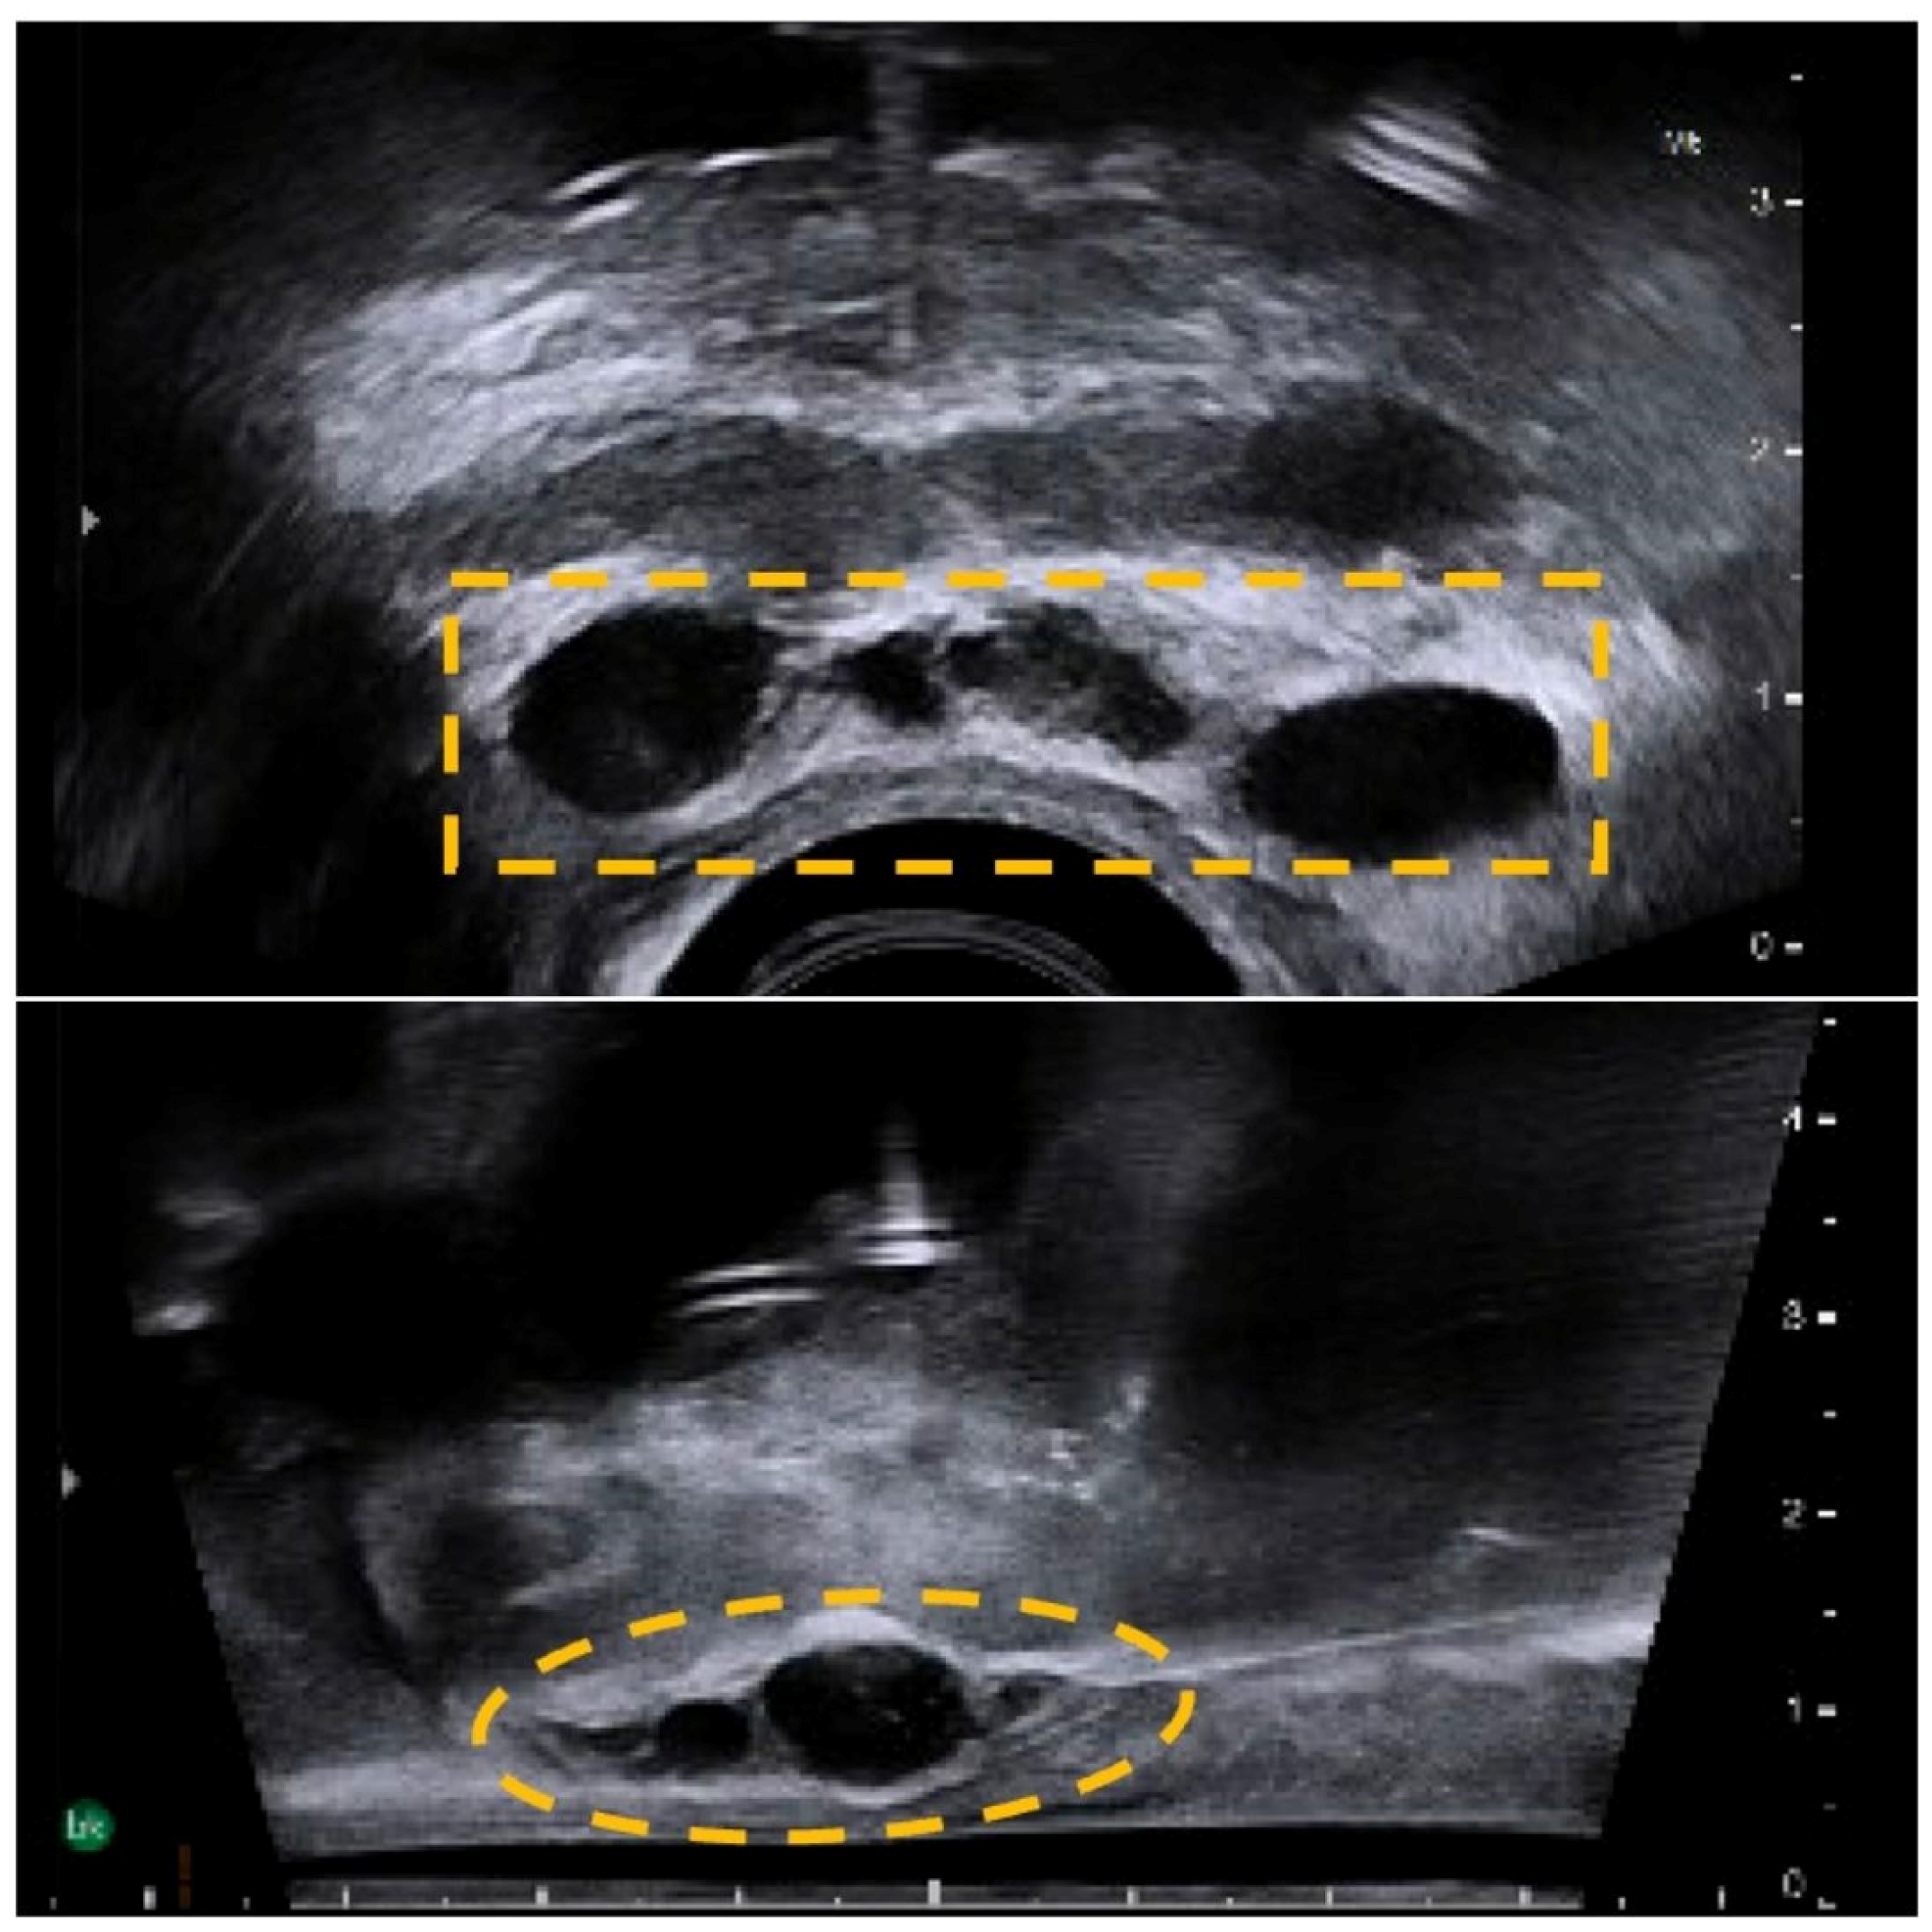

An interval CT KUB performed three months after showed new acalculous bilateral mild hydroureteronephrosis with apparent eccentric irregular thickening of the superior urinary bladder wall, suggestive of urinary bladder neoplasm. This was confirmed on histology (TURBT) as a pT2 muscle-invasive bladder cancer (MIBC). Post-multidisciplinary team discussion, the decision was made to perform an SCP with HA rectal spacer infiltration into the Denonvilliers’ space two weeks prior, for rectal protection. The HA rectal spacer was injected into the perirectal fat under sagittal TRUS guidance using a midline 18G needle inserted transperineally, which showed good separation of the perirectal tissue at the base and mid-gland of the prostate (Figure 1).

Figure 1. An anechoic HA rectal spacer (yellow dotted line) is injected into the Denonvilliers’ space as seen on TRUS, showing good separation between the perirectal tissue at the base and mid-gland of the prostate.